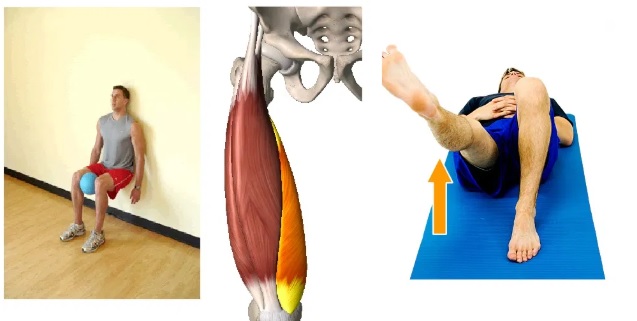

Knee Flexion Supine: Improves mobility in a stiff joint. Must be performed 30s times daily, holding for 2-3 seconds and repeating 2-3 times.

Inner Range VMO Quadriceps Lying: Activates the vastus muscles and significantly reduces the anterior knee pain. Must be performed 10-15s times daily, holding for 2-3 and repeating for 3-10 times.

VMO Strengthening Standing: Helps to strengthen muscles in the thigh, which is particularly important for knee rehabilitation. Must be performed 10-15s times daily, holding for 2-3 and repeating for 3-10 times.

VMO Strengthening Sitting: This exercise helps to stabilize your kneecap and keep it in line when you bend you knee. Must be performed 10-15s times daily, holding for 2-3 and repeating for 3-10 times.

VMO Strengthening Squat: Helps in upward tracking of the knee cap in the femoral groove. It is a common weight-bearing exercise. Must be performed 10-15s times daily, holding for 2-3 and repeating for 3-10 times.